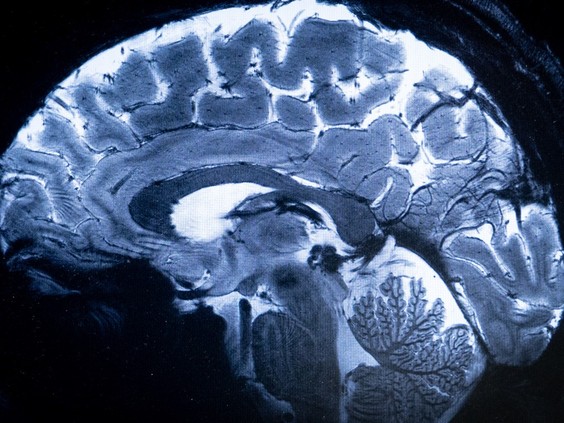

![]() |

| A new study published in JAMA Neurology debunks “an alleged ‘mystery’ neurological illness” that emerged in New Brunswick six years ago. Photo by ALAIN JOCARD /AFP via Getty Images |